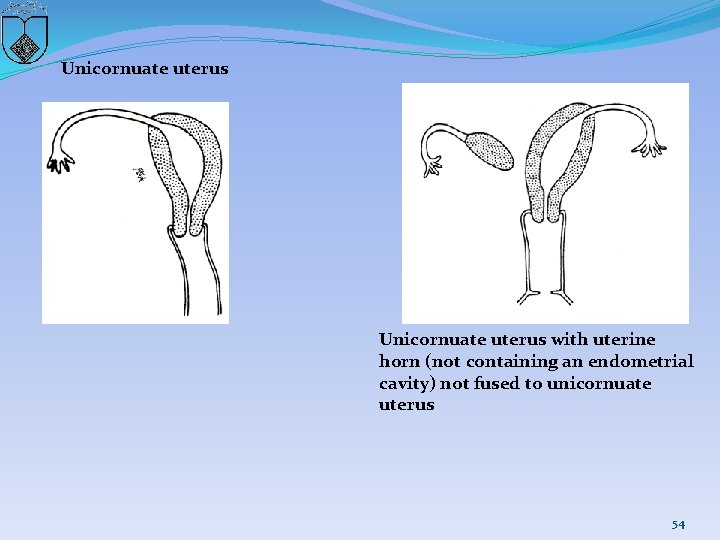

Unicornuate uterus with uterine horn (not containing an endometrial cavity) not fused to unicornuate uterus 54